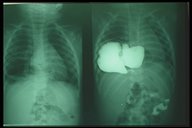

After completion of the plication of diaphragm, the diaphragm is strengthened and flattened

After completion of the plication of diaphragm, the diaphragm is strengthened and flattened flattened (right) and chest X-ray showed that the affected diaphragm was at the normal level.